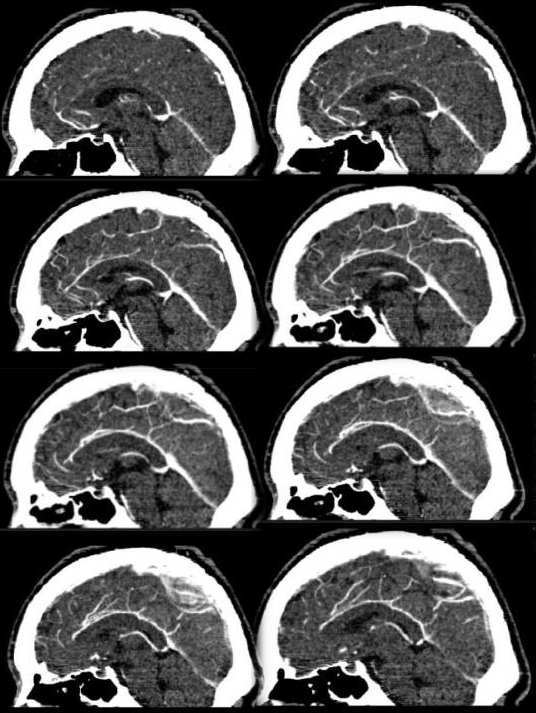

2:矢状位+c:矢状窦还没强化完全,顶部迂曲的血管网已经强化良好,强化速度明显快。靠近上矢状窦并可见迂曲增强的小团状血管影

3:矢状cta:顶部血管强化程度明显强于正常脑血管,呈迂曲不规则状。

综上考虑:顶部脑血管畸形以avm可能性大。并两侧顶叶局限性缺血性脑萎缩

鉴别:脑膜瘤--横扫未见瘤体及水肿。矢状位未见瘤体,未见肿瘤引起的占位效应及白质塌陷